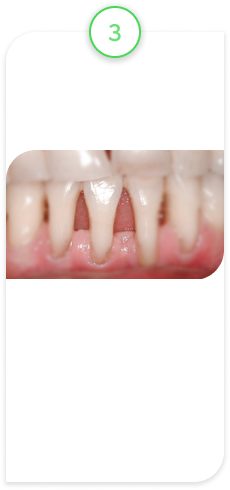

Случай из практики.

Наращивание десны

Пациент обратился с жалобами на оголенный корень зуба, повышенную чувствительность, на неэстетический вид зуба, так как зуб стал выглядеть длиннее, чем раньше.

После обследования поставили диагноз — рецессия десны.

Это патологическое состояние, при котором десна опускается вниз, корень зуба оголяется, появляется чувствительность зуба, эстетический дефект и возрастает риск развития другого патологического состояния — кариеса корня. В свою очередь, кариес корня — это показание к удалению зуба.

В данном клиническом случае провели микрохирургическую операцию по наращиванию десны с применением специального микроскопа. Это дало хороший, долгосрочный прогнозируемый результат.

ВАЖНО! Нужно понимать, что не у каждого оголенного корня можно нарастить десну. Ключевой фактор — стадия, на которой вы обратились. Есть стадии, на которых это невозможно, и единственным вариантом является УДАЛЕНИЕ ЗУБА!

Исходное состояние